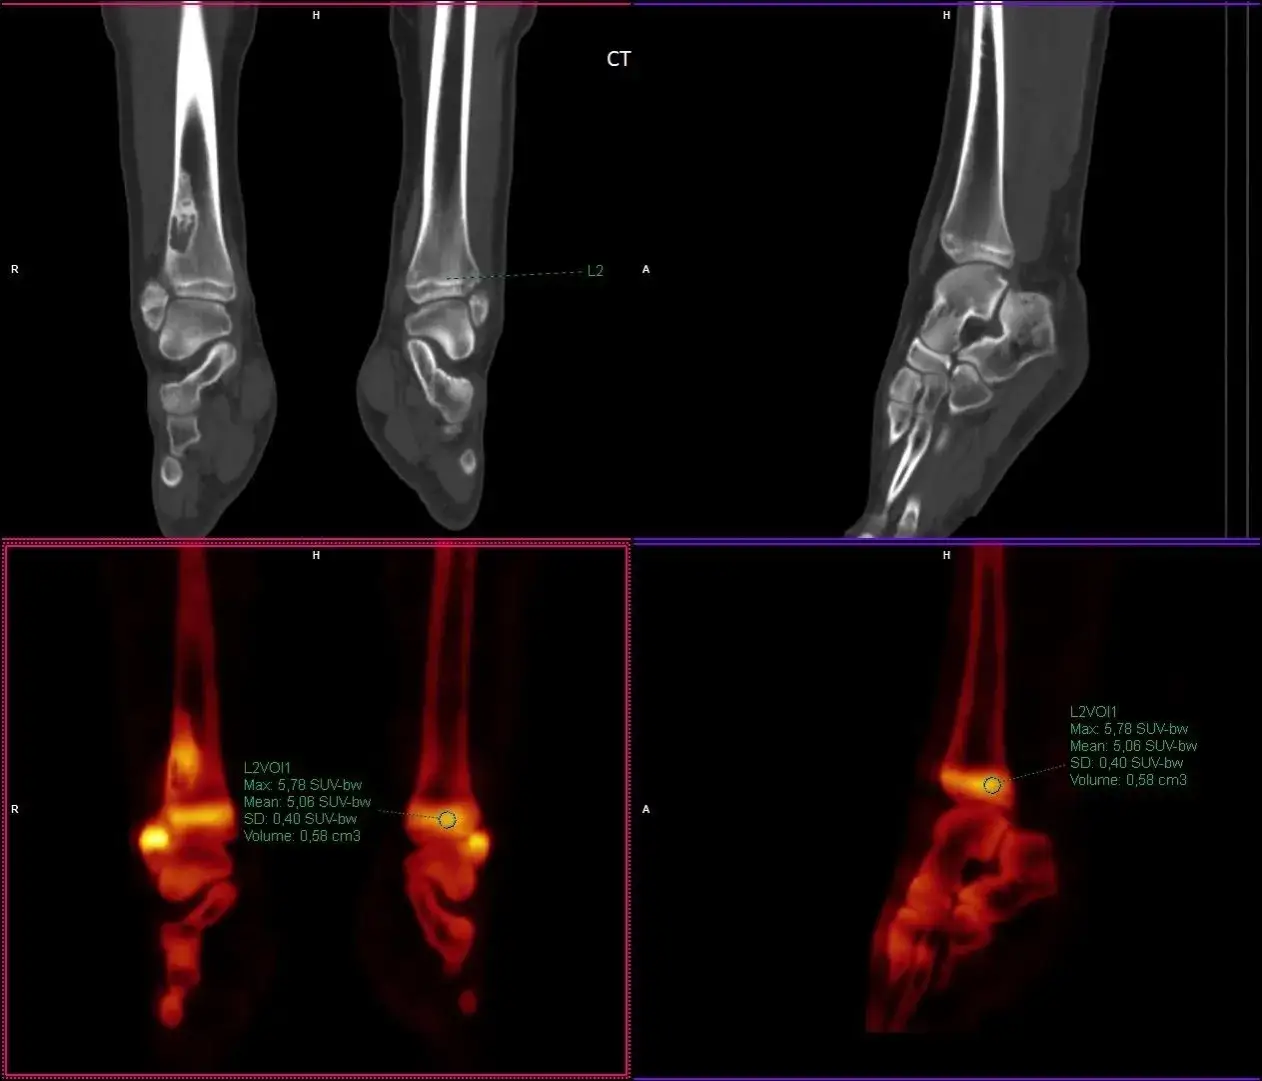

Podczas interpretacji wartości SUV, ważne jest, aby zwrócić uwagę na kilka aspektów. Po pierwsze, wartości SUV mogą się różnić w zależności od rodzaju tkanki oraz stanu zdrowia pacjenta. Na przykład, zdrowe tkanki mogą mieć wartości SUV poniżej 2,5, podczas gdy w tkankach nowotworowych wartości te mogą przekraczać 7. Zrozumienie tych różnic jest kluczowe dla właściwej analizy wyników badań.

Wartości SUV (Standardized Uptake Value) różnią się w zależności od rodzaju tkanki oraz jej stanu. Normalne wartości SUV dla zdrowych tkanek, takich jak wątroba czy nerki, zazwyczaj nie przekraczają 2,5. W przypadku tkanek nowotworowych, jak rak kory nadnercza, wartości te mogą być znacznie wyższe, często przekraczając 7. Zrozumienie tych wartości jest kluczowe dla lekarzy, ponieważ pomaga w identyfikacji obszarów patologicznych.

Wartości SUV są niezwykle pomocne w wykrywaniu nieprawidłowej aktywności metabolicznej w tkankach. Na przykład, w badaniach PET przeprowadzonych na pacjentach z rakiem płuc, wartości SUV w obszarach nowotworowych były znacznie wyższe niż w zdrowych tkankach. W jednym z przypadków, pacjent z rakiem płuc wykazał wartość SUV równą 8,5 w zmienionym obszarze, co potwierdziło obecność nowotworu. Taka informacja jest kluczowa dla lekarzy, którzy mogą podjąć decyzję o dalszym leczeniu.